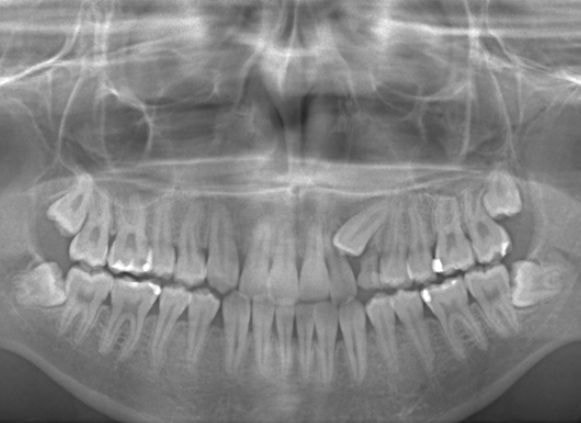

やはり統計通り、左上3番の埋伏です。

左上2番の歯根吸収が認められますが、保存不可能なレベルではありません。

治療中のレントゲンです。

7番、8番の状態や歯根のパラレリング(平行性)をチェックしています。

左上2番の歯根の状態もなんとかもちそうです。

上顎劣成長症例ですが、鼻腔の状態も悪くありません。